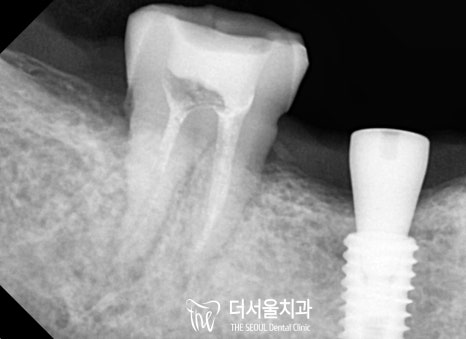

더 서울에서 정확한 진단을 위해

엑스레이 촬영을 진행한 결과,

하악 우측 잔존 어금니는 심한 충치로 인해

병소가 치수까지 감염되어 있었습니다.

그 이유는 픽스쳐가 뼈에 붙는 최소 기간이 2달이기 때문에

디지털임플란트 를 제일 먼저 하기로 했기 때문에

정확한 식립을 위한 분석을 시작했습니다.

이후, 미리 제작된 가이드를 사용하여

무절개 방식으로 단단하게 심어드렸습니다.